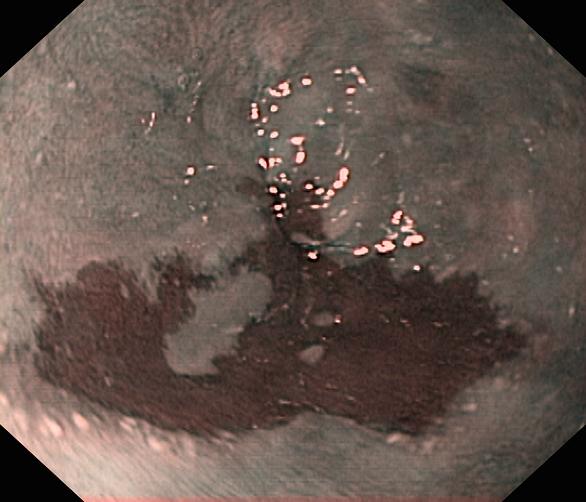

Przełyk Barretta